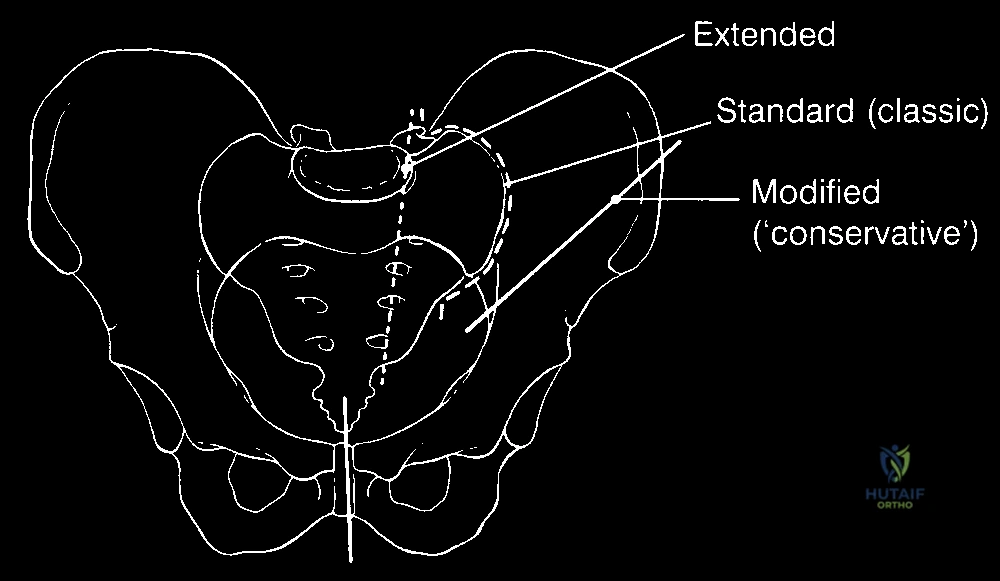

لماذا تُسمى هذه العملية بـ "بتر النصف الحوضي بالسديلة الخلفية"؟

عند إزالة نصف الحوض والطرف السفلي، يتبقى جرح مفتوح ضخم جداً في جانب الجسم. لا يمكن إغلاق هذا الجرح ببساطة. لذلك، يعتمد الجراح الماهر على تصميم هندسي تشريحي مسبق.

يقوم الدكتور هطيف برسم خطوط الشق الجراحي بحيث يتم الحفاظ على الجلد والعضلات الموجودة في الأرداف (الجهة الخلفية) - بشرط أن تكون خالية من الورم. هذه الأنسجة المحفوظة تُسمى "السديلة" (Flap). بعد إزالة العظام والورم، يتم طي هذه السديلة للأمام لتغطية الأعضاء الداخلية وتشكيل جدار قوي ووسادة نسيجية متينة.

يبدأ الدكتور هطيف بعمل شق جراحي أمامي يمتد فوق الرباط الأربي. الهدف الأول والأهم هو تحديد الأوعية الدموية الرئيسية (الشريان والوريد الحرقفي الأصلي أو الظاهر).

يتم ربط هذه الأوعية الدموية وقطعها بحذر شديد. هذه الخطوة حاسمة جداً لمنع النزيف الكارثي أثناء المراحل اللاحقة من العملية.

الخطوة الثالثة: الشق الخلفي ورفع السديلة

يتم الآن قلب المريض قليلاً لإجراء الشق الخلفي. يتم رفع الجلد والدهون وعضلة الألوية الكبرى (Gluteus Maximus) ككتلة واحدة (السديلة الخلفية)، مع الحفاظ على التروية الدموية الخاصة بها لضمان عدم تموتها لاحقاً.

الخطوة الرابعة: قص العظام (Osteotomy) وفصل الحوض

باستخدام مناشير عظمية متقدمة، يتم فصل عظام الحوض عن العمود الفقري (عند المفصل العجزي الحرقفي) وفصلها من الأمام (عند الارتفاق العاني). يتطلب هذا دقة متناهية لضمان استئصال الورم بالكامل دون المساس بالأعضاء الداخلية في الحوض (مثل المثانة والمستقيم).